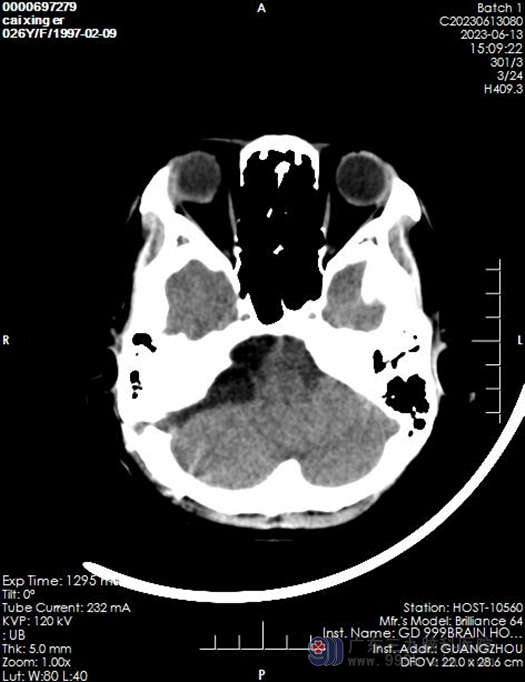

近日26岁的蔡女士,在家中休息突然出现头痛头晕,呕吐一次,蔡女士怀着焦虑紧张的心情,随即就诊于当地诊所,诊断“胃炎”。吃了胃药一段时间以后发现症状并未缓解, 甚至还出现了加重的症状,这让蔡女士一家都很是担心。为进一步诊疗,终于在家人的劝说下来到了三九脑科医院就诊,诊断出“右侧桥小脑角区占位”,随即收入神经外十科。

让我们来了解一下桥小脑角区占位:桥小脑角区是由前内侧的脑桥外缘、前外侧的岩骨内缘以及后下方的小脑半球前外侧缘构成一个锥形窄小的空间。包含了听神经、面神经、三叉神经及小脑前下动脉等,如果局部出现肿瘤或其他占位,会导致患者出现桥小脑角综合征,桥小脑角综合征主要症状是耳鸣,进行性耳聋、面瘫、同侧肢体的共济失调。表皮样囊肿好发于脑部的桥小脑角、鞍区和颞极等处,它囊壁薄,由一层表皮组织形成,囊内有上皮碎屑,角蛋白和胆固醇组成。囊肿不规律,沿缝隙生长是它特点。常见于后颅窝,其次,为额叶底部或颞极。如果形成脑积水导致颅内压增高还会出现头痛、恶心、呕吐。因为症状和胃炎很像似,患者常常觉得没什么问题,以为是胃炎。很容易忽略掉,从而影响患者后续病情治疗。

患者入院以后,欧阳辉教授带领神经外十科医生团队,对患者进行详细的检查,可考虑行“右侧桥小脑角区占位切除术”,并为患者制定了手术方案。实施手术:采用右侧乙状窦后入路,采用全麻麻醉方式行右侧桥小脑角区占位切除术,在医生的沟通下,家属同意手术。